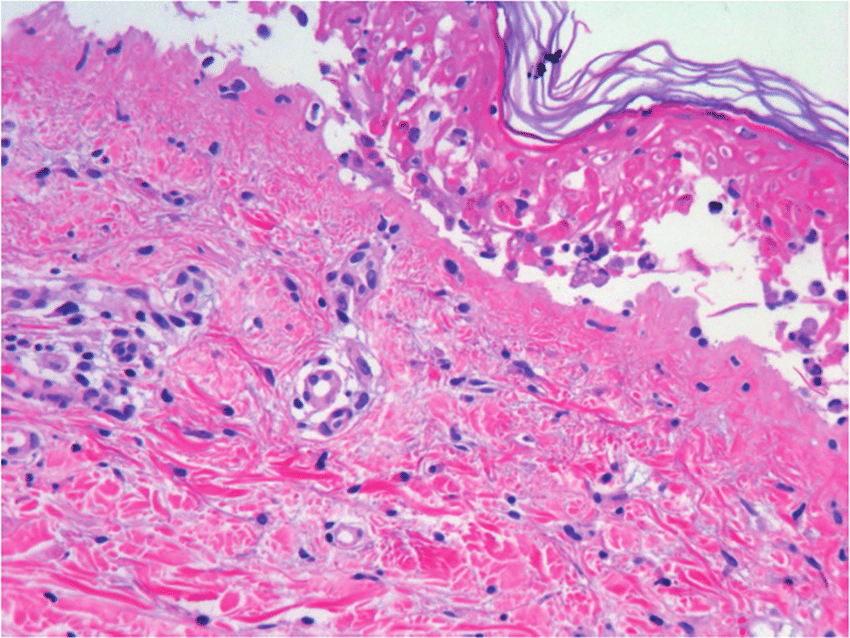

En general, su etiología y presentación son consensuadas, definiéndose como una necrólisis generalizada de la epidermis que se produce como una respuesta inmune descontrolada a un fármaco específico o a uno de sus metabolitos, destacando el cotrimoxazol y el alopurinol como los más importantes. Esta necrólisis conduce a un desprendimiento masivo de la capa epidérmica de la piel, con mayor incidencia en el torso, miembros superiores y cara. Eur. Burn J. 8 agosto 2022